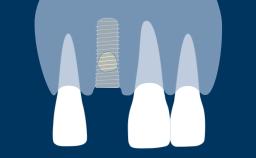

拔牙后,支撑牙齿的牙槽骨会随着时间的推移而发生吸收。这种吸收会导致牙槽骨量减少,如此右上中切牙缺失的临床示例所示。颊舌向骨宽度显著减小,这与将种植体植入以修复为导向确定的正确三维位置的口腔种植基本要求存在冲突。当牙槽骨发生吸收后,通常需要增加骨量以确保可以正确植入种植体且种植体完全嵌入骨中。本模块将介绍一种称为引导骨再生 (GBR) 的特定骨增量技术。